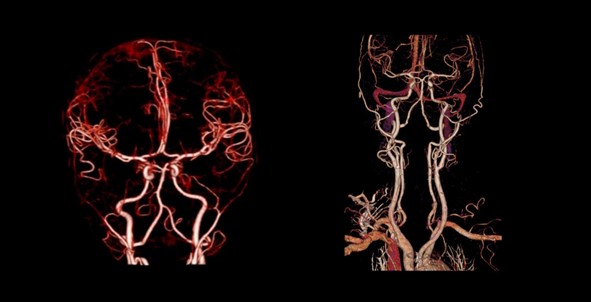

Khả năng chụp mạch máu xóa nền giúp chẩn đoán phát hiện các bất thường về mạch máu.

Ảnh chụp mạch máu xóa nền từ máy Aquilion Prime SP